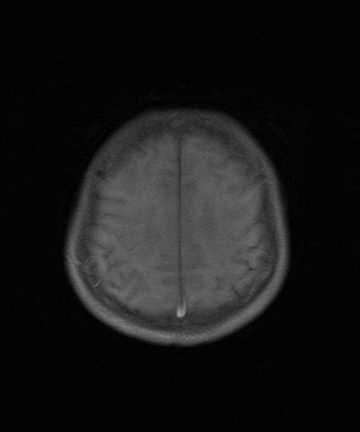

标题: MRI2064:少见病例。男性52,视力下降多年。 [打印本页]

标题: MRI2064:少见病例。男性52,视力下降多年。

四脑室区见混杂信号占位影,脑室系统扩张明显,临近结构显著受压称位,患者52岁,多考虑室管膜瘤可能性大

考虑第四脑室室管膜瘤并阻塞性脑积水。

考虑第四脑室室管膜瘤并梗阻性脑积水;部分性空蝶鞍;左侧上颌窦粘膜下囊肿。